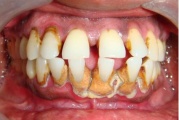

Krooniline parodontiit

Krooniline parodontiit on mikroobide poolt põhjustatud hammaste tugikudede põletik, mille tulemusena tekib progresseeruv alveolaarluu (nähtav röntgenograamil) ja periodontaalligamendi destruktsioon, igemetaskute moodustumine, igeme retsessioon või mõlemad kahjustused kombineeritult. Loe edasi »

- igemed veritsevad (19)

- igemed punetavad (21)

- ige on paistes (mädapunn)

- igemed on tursunud/vohavad (17)

- igemepealne hambakivi (5)

- igemealune hambakivi (4)

- halb hingeõhk / suu haiseb (12)